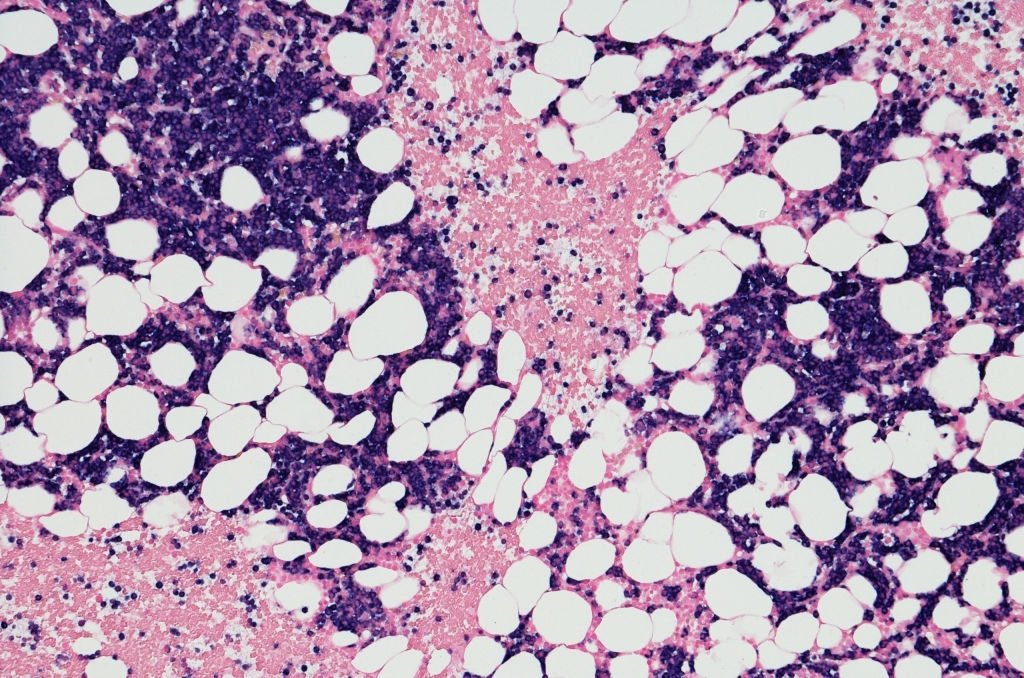

Micrograph of myeloma neoplasm bone marrow biopsy. Kappa positive insitu hybridization (ISH positive)

Role of bone marrow transplant in multiple myeloma Bone marrow transplant/ stem cell transplant

A procedure of infusing healthy blood-forming stem cells into human body to replace damaged or diseased bone marrow. Bone marrow transplants may use: cells from your own body (autologous transplant)…